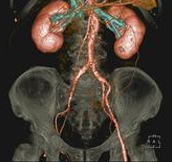

Body angiography with automatic table removal ? colored volume rendering reconstruction. Case: Aortic dissection. Left common iliac artery occlusion. Scanning: P0.83, 0.5s, 360mA, 100kV, weight 80kg, contrast 80cc